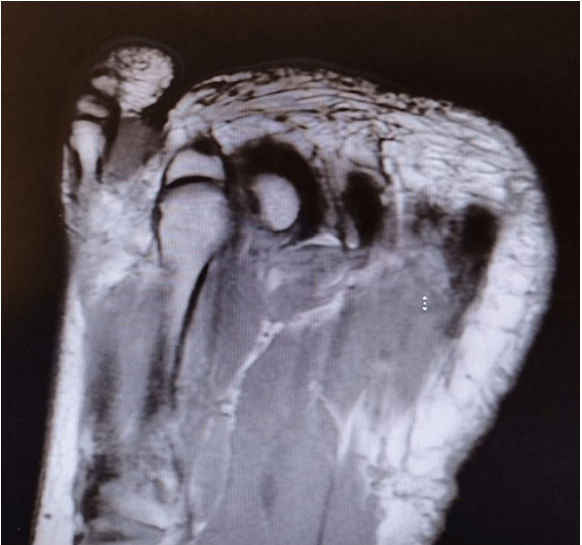

MRI: Revealed an oval-shaped mass on the medial and dorsal aspect of the fifth toe's proximal phalanx, measuring approximately 2 cm. It exhibited intermediate low signal intensity on T1-weighted images and mildly higher heterogeneous intermediate signal intensity on T2-weighted images, closely associated with the flexor tendon (Figures 1, 2 & 3)

FIGURE 1: MRI finding of the lesion (lateral view)